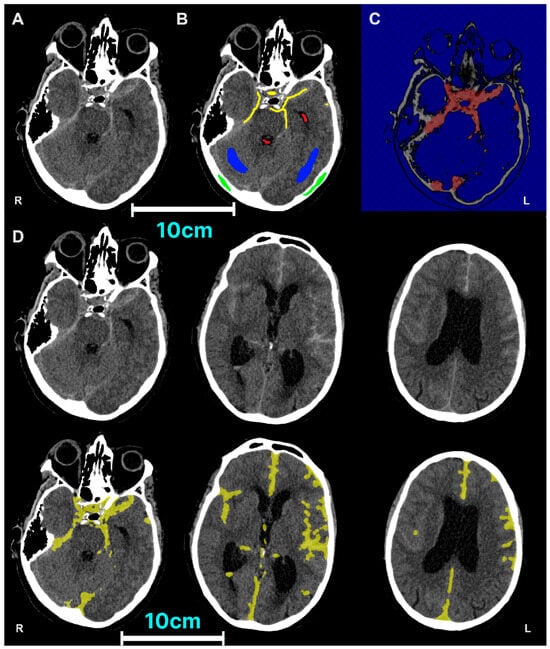

| Subarachnoid Haemorrhage (SAH) | CT non-contrast | Acute haemorrhage will be present with 15–25 Hounsfield Units (HU) of greater density than normal grey and white matter on a CT scan [36]. Anatomically, SAH is typically found present in the interpeduncular cistern, the Sylvian fissure, the occipital horns of the lateral ventricles and the deep sulci on each side of the medial longitudinal fissure [37]. |